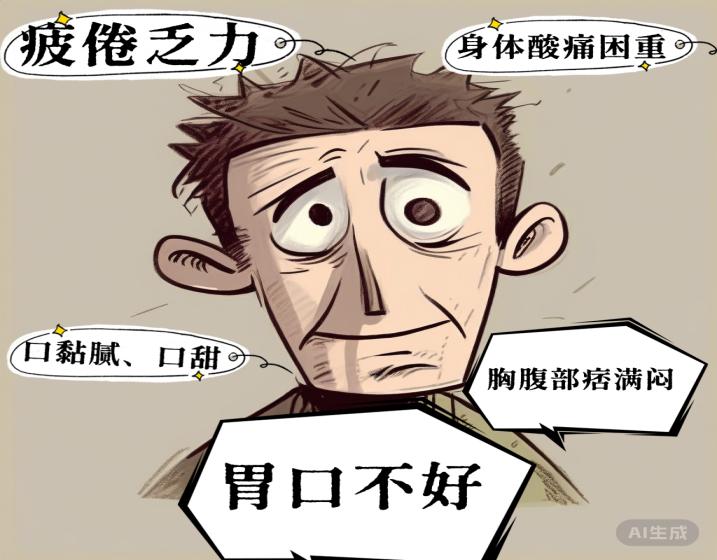

重症医学科 何虹材 中西医结合主治医师四川盆地气候全年温暖湿润,年均温16-18℃,冬暖夏热,降雨量多,晴天少,温暖湿润的气候造就了物产丰富的“天府之国”,但也给盆地人民带来了“幸福的烦恼”,那就是盆地人民的“湿气”重,每到夏季或秋雨绵绵的季节,则出现浑身酸重乏力,提不起精神。现代研究表明“湿气”和...

重症医学科 何虹材 中西医结合主治医师四川盆地气候全年温暖湿润,年均温16-18℃,冬暖夏热,降雨量多,晴天少,温暖湿润的气候造就了物产丰富的“天府之国”,但也给盆地人民带来了“幸福的烦恼”,那就是盆地人民的“湿气”重,每到夏季或秋雨绵绵的季节,则出现浑身酸重乏力,提不起精神。现代研究表明“湿气”和...